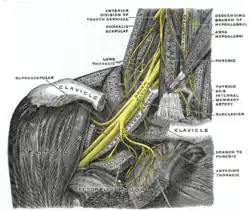

The right brachial plexus with its short branches, viewed from in front. Levator scapulae muscle

Levator scapulae muscle Brachial plexus. Deep dissection.